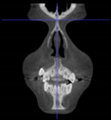

Three points determined the Acta plane: O, F right (FR), and F left (FL) (Table 2). Point O is the midpoint between the most craniodorsal point of the dorsum Sella and the most posterior dorsal point of the Basion in the midsagittal plane (Figure 1). Both points F are a result of the intersection between two lines: the line that connects the most inferior points of the lower orbital margins, right and left, and a line perpendicular to this line that runs through the most external points of the orbital margins, right and left (Figure 2). The new transverse reference plane, the Acta plane (Figure 2), is created by connecting the O-point (Figure 1) with FR and FL (Figure 2).

Figure 2.

(A) Construction of the F-points (right and left), frontal view. The F-points are originated from the intersection between the line connecting points A (the most inferior point of the lower orbit) and the perpendicular line to it that passes through points B (most external/lateral point of the Orbita). (B) Transverse view of the ACTA plane.

Different from the majority of the existing planes, the Acta plane was idealized for 3D use. Therefore, our goal was to determine both external and internal references in the skull. External references were determined from the orbital rim. The first reference line originated from the connection between the most inferior points of the left and right lower orbital margins. In order to keep the head facing forward, a line was traced perpendicularly to the first line, running through most of the external points of the left and right orbital margins. The intersection of these two lines resulted in point F, which orients the CBCT scan in the X-axis and Y-axis.